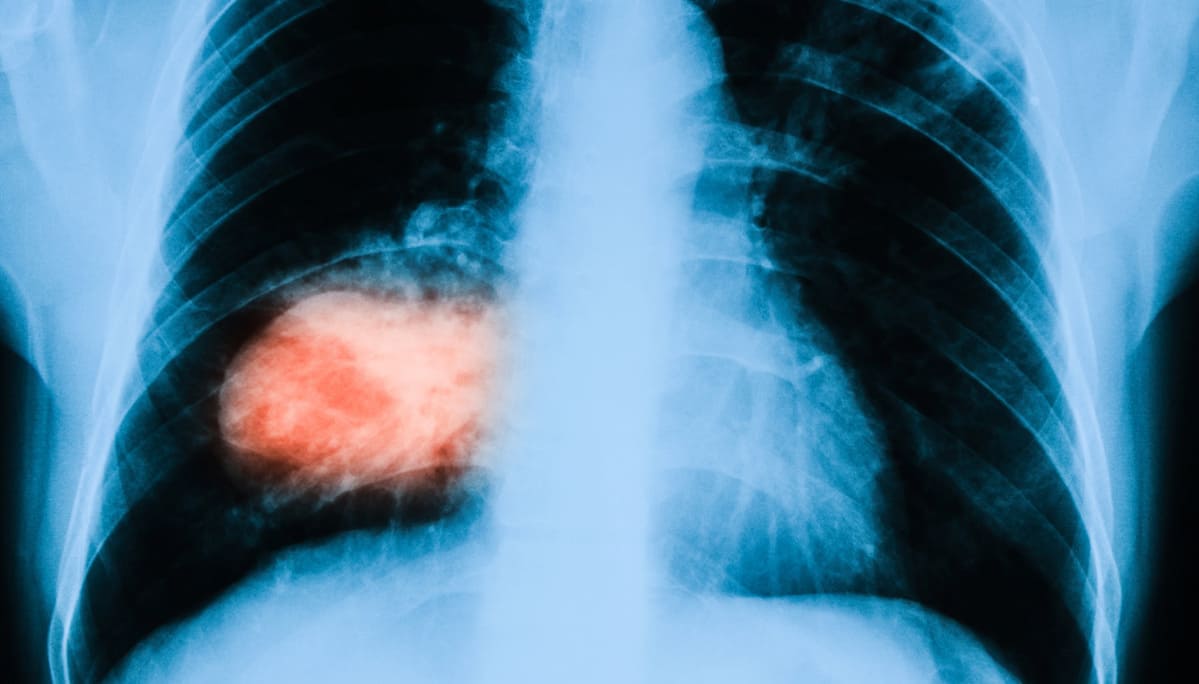

Pasi A. Jänne, direttore del Lowe Center for Thoracic Oncology, Dana Farber Cancer Institute, e professore di medicina alla Harvard Medical School di Boston, ha presentato i risultati relativi a 79 pazienti con NSCLC ( cancro del polmone non a piccole cellule, non-small-cell lung cancer) fino al 30 agosto 2020 e ha affermato che su 51 pazienti il 45% ha avuto una risposta positiva:

Su 51 pazienti il 45% ha ottenuto una risposta obiettiva, il che significa che i loro tumori si sono ridotti del 30% o più e non sono cresciuti o diffusi in altre parti del corpo.

Il tasso di controllo della malattia era del 96%, il che significa che 49 dei 51 pazienti hanno mostrato una risposta parziale o completa o hanno avuto una malattia stabile.

Tra i 14 pazienti arruolati nella fase 1/1b dello studio, seguiti per un periodo di tempo più lungo (tempo mediano di 9,6 mesi), sei (43%) hanno mostrato una risposta obiettiva e in quattro di questi sei pazienti la durata del trattamento era superiore agli 11 mesi.

Sono stati analizzati anche gli effetti collaterali correlati al trattamento in tutti i 110 pazienti inclusi nella fase 1/1b e 2 dello studio. I più comuni sono stati nausea nel 54% dei casi, diarrea nel 51%, vomito nel 35% e stanchezza nel 32%. L’unico effetto collaterale grave che si è verificato in due pazienti è stato il basso contenuto di sodio nel sangue.